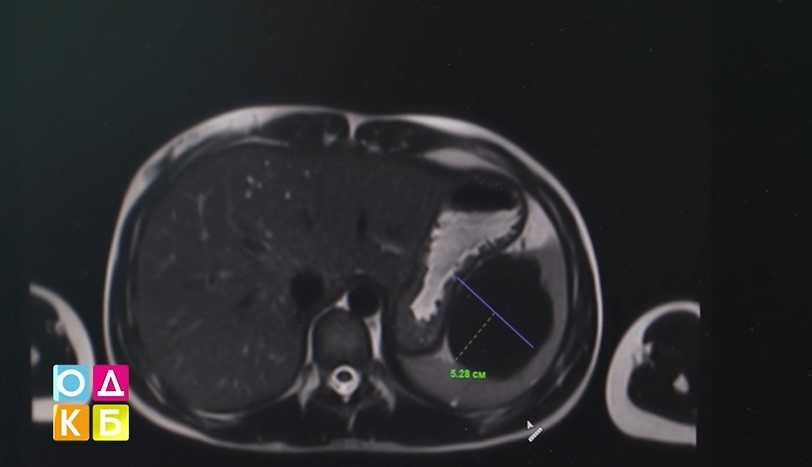

Как объяснил заведующий отделением общей и гнойной хирургии Максим Тарасов, относительно размеров селезёнки (10 на 10) киста была большой (7 на 7), к тому же располагалась в воротах селезёнки, где проходят сосуды. Селезёнку пришлось удалить вместе с кистой.

Фото: КОДКБ им. Ю. А. Атаманова / Telegram